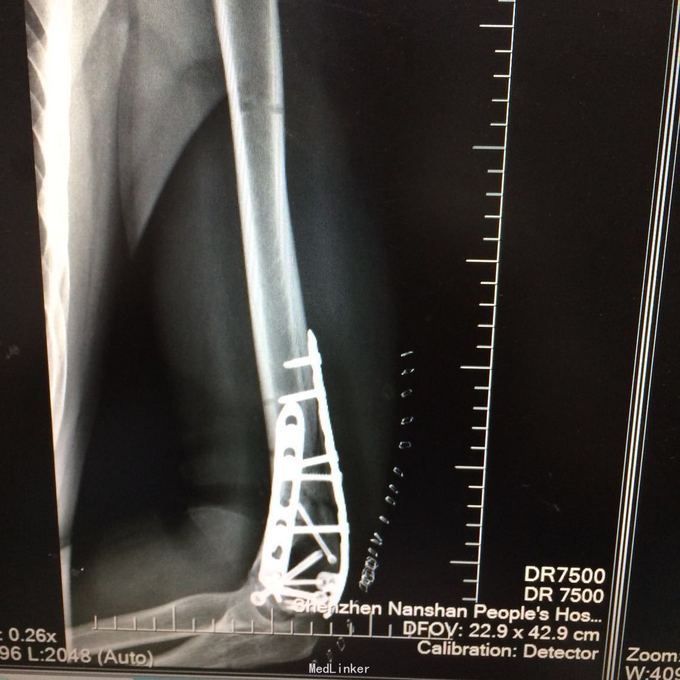

1、左肱骨远端粉碎性开放性骨折;2、左肘关节半脱位;3、左手第4、5掌骨远端骨折;4、右手第1、3、4远节指骨骨折;5、右手第5中节、远节指骨骨折;6、鼻部软组织挫裂伤;鼻中隔骨折;7、右侧第3--7肋骨折;8、左跟骨粉碎性骨折;9、左眉弓软质挫裂伤;10、左肺挫伤;11、脑震荡。 1.完善三大常规、PT四项、生化等各项常规检查; 2.完善CT检查,予抗破伤风、抗感染、镇痛、止血等对症支持治疗; 3.请口腔、耳鼻喉、眼科等相关科室会诊; 4.请示上级医师,指导下步治疗。 手术时间:2015年11月15日 术后诊断:左肱骨远端开放性粉碎性骨折 麻醉方式:全身麻醉 手术名称:左肱骨远端开放性粉碎性骨折清创缝合外固定架固定术 手术时间:2015年12月25日 术后诊断:左肱骨远端粉碎性骨折 麻醉方式:臂丛麻醉 手术名称:左肱骨远端粉碎性骨折切开复位内固定术 。 手术时间:2015-12-3 术后诊断:左跟骨粉碎性骨折;左肱骨远端粉碎性开放性骨折;左肘关节半脱位;左手第4、5掌骨远端骨折;右手第1、3、4远节指骨骨折;右手第5中节、远节指骨骨折;右足拇趾撕脱骨折并趾间关节脱位;鼻部软组织挫裂伤;鼻中隔骨折;右侧第3--7肋骨折;左眉弓挫裂伤;左肺挫伤;脑震荡。 麻醉方式:腰硬联合 手术名称:左跟骨粉碎性骨折切开复位钛板内固定术